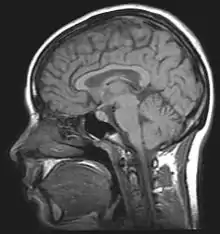

Brain structures

The leading experimental technique for studying proactive interference in the brain is the “recent-probes” task. Initially, this is when participants must commit a set of items to memory. They then ask them to recall a specific item. Assessing them is shown by a probe.[10] Thus, using recent-probes task and fMRIs, the brain mechanisms involved in resolving proactive interference identify as the ventrolateral prefrontal cortex and the left anterior prefrontal cortex.[11]

Retroactive Interference has been localized to the left anterior ventral prefrontal cortex by magnetoencephalography (MEG) studies investigating Retroactive Interference and working memory in elderly adults.[23] The study found that adults 55–67 years of age showed less magnetic activity in their prefrontal cortices than the control group. Executive control mechanisms are located in the frontal cortex and deficits in working memory show changes in the functioning of this brain area.[23]